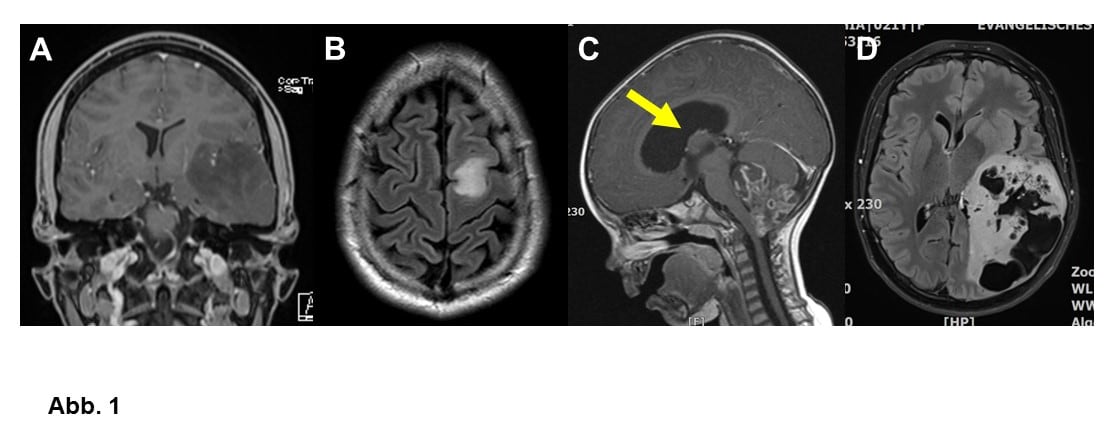

Die Ursprungszellen der Gliome sind die Stützzellen des zentralen Nervensystems, d. h. die Gliazellen. Je nach vermuteter Ursprungszelle (Astrozyt oder Oligodendrozyt) unterscheidet man zwischen Astrozytomen und Oligodendrogliomen (Abb. 1A und B). Manchmal rechnet man auch die Ependymome (Abb. 1C) zu den Gliomen, Ependymome entstehen aus den Zellen, die Hirnkammern auskleiden (Ependym). Es gibt sogenannte glioneuronale Tumoren, die von Zellen abstammen, aus denen noch sowohl Gliazellen als auch Nervenzellen (Neurone) werden können (Abb. 1D).

Gliome werden aber nicht nur nach ihren mutmaßlichen Ursprungszellen, sondern auch nach Wachstumgeschwindigkeit bzw. Bösartigkeit eingeteilt. Man unterscheidet hier die WHO-Grade I (gutartig) bis IV (sehr schnell wachsend, bösartig; Abb. 1-4). Die Verwendung von WHO-Graden erlaubt auch, dass häufige Phänomen der Entartung (maligne Progression) zu beschreiben. Viele Astrozytome und Oligodendrogliome WHO Grad II und III können sich Verlauf in bösartigere WHO Grad III bzw. Grad IV-Tumore (Glioblastome) umwandeln. Häufiger sind allerdings primäre (direkt entstandene) Glioblastome (Abb. 2-4).

A. Astrozytom WHO-Grad II bei einem 23-jährigen Mann, der mit mehreren Krampfanfällen auffällig wurde.

B. Kleines Oligodendrogliom WHO-Grad II bei einem 36-jährigen Mann. Das MRT wurde zur Abklärung eines erstmaligen epileptischen Anfalls durchgeführt.

C. Einjähriges Kind mit einem anaplastischen Ependymom WHO-Grad III. Der Tumor behindert den Hirnwasserabfluß, was zu einem Hydrocephalus (Pfeil) geführt hat. Ependymome bei Erwachsenen sind meist kleiner.

D. Gangliogliom WHO-Grad I bei einer 21-jährigen Frau. Auch dieser Tumor wurde durch einen epileptischen Krampfanfall auffällig.